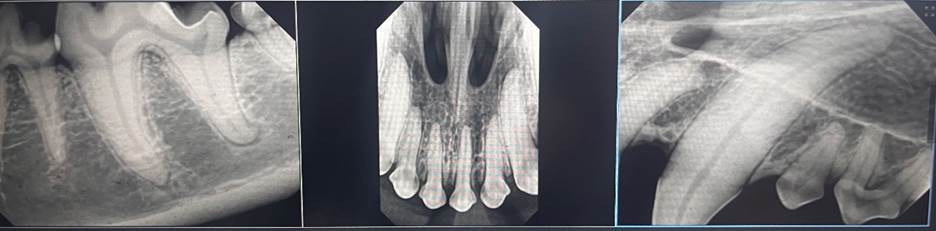

Digital dental radiography allows us to detect hidden issues like root abscesses, fractures, and bone loss. With this technology, we can create a precise oral treatment plan tailored to your pet’s needs and comfort.

Your pet’s dental procedure begins with a full oral exam and customized treatment plan from the veterinarian. Our licensed veterinary technicians then perform a thorough dental cleaning using ultrasonic scaling and polishing, charting the teeth and taking digital x-rays of problem areas. The veterinarian reviews the x-rays and performs any necessary surgical extractions.